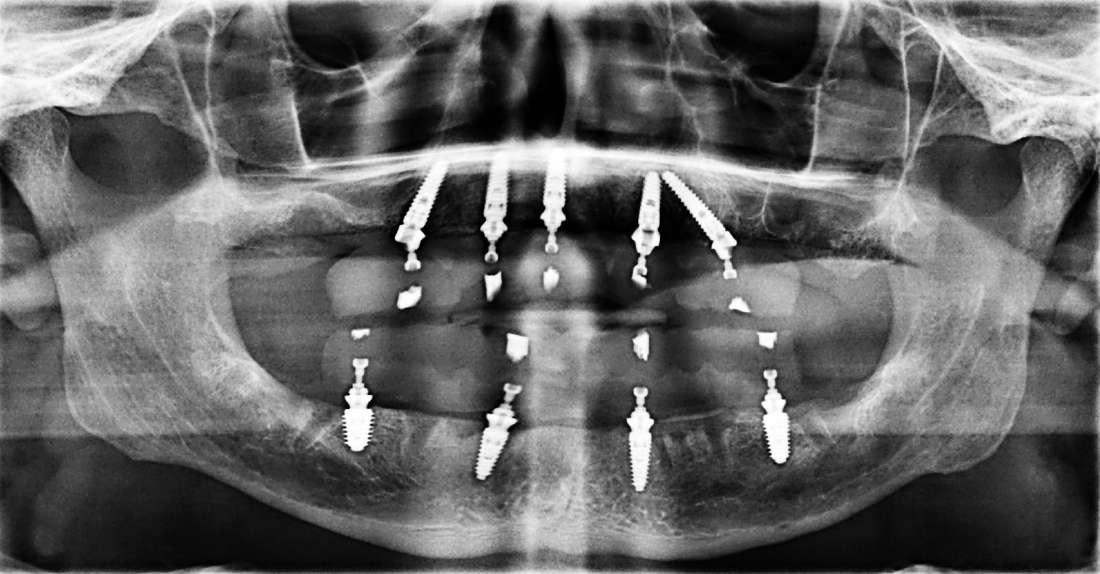

Upper and Lower All-on-4 Dental Implants

Life changing procedure for our wonderful patient. His teeth were loose and infected and could not be saved. Dr. Vishal Advani placed upper and lower implants after removing the teeth.  Temporary bridges were placed immediately, all in one day.  After full healing, the permanent zirconia bridges were placed by Dr. Advani.  The patient could not have been happier